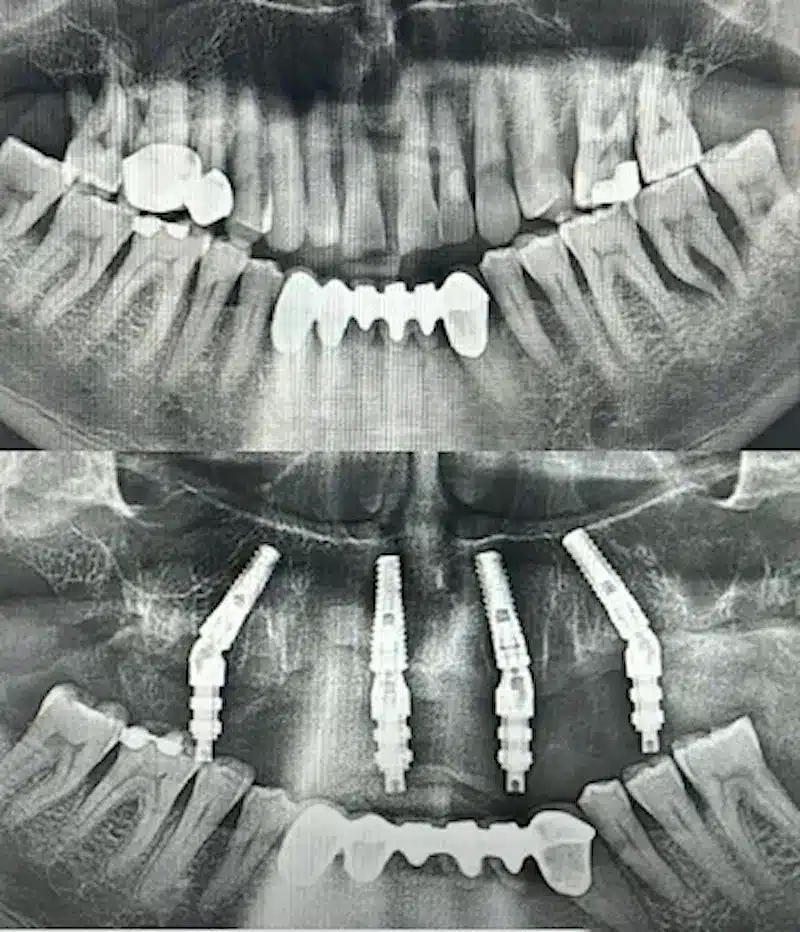

Dr. Seden Aksu is a specialist in modern implantology and surgical dentistry with extensive experience in the management of complex clinical cases. In her practice, she applies comprehensive surgical planning, minimally invasive techniques, and advanced regenerative technologies aimed at restoring both the function of the dentoalveolar system and the aesthetics of the smile. Dr. Aksu has significant experience in performing implant procedures, bone augmentation, and periodontal surgery, including the treatment of patients with severe bone loss. The primary goal of her work is to achieve stable, long-term outcomes in implant rehabilitation and the restoration of oral tissue health.